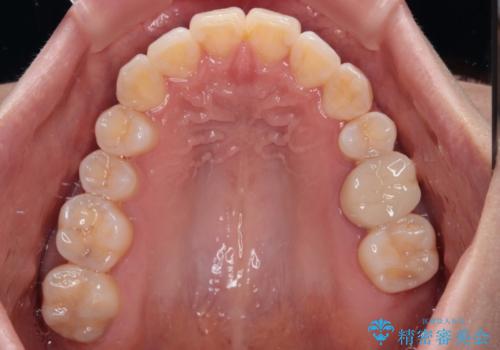

八重歯と開咬の抜歯矯正 ワイヤー装置を併用したインビザライン矯正治療

- 咬み合わない前歯と八重歯などのデコボコを気にして来院された患者様です。

上下前歯の位置を比較すると上顎が前方にあり、デコボコ改善でより上顎が前方に行く可能性があります。

開咬の改善にはインビザラインが有効であり、インビザライン単体での治療を検討しましたが、上顎前突を回避するために上顎左側第一小臼歯抜歯を行うこととしたため、補助装置とワイヤー矯正を併用した上で、インビザラインによる矯正治療を行うこととしました。

インビザライン矯正治療では、臼歯の圧下による前歯部の早期接触が大きな問題となっています。開咬では、その臼歯圧下を逆手にとって前歯部の非接触を改善させることができます。